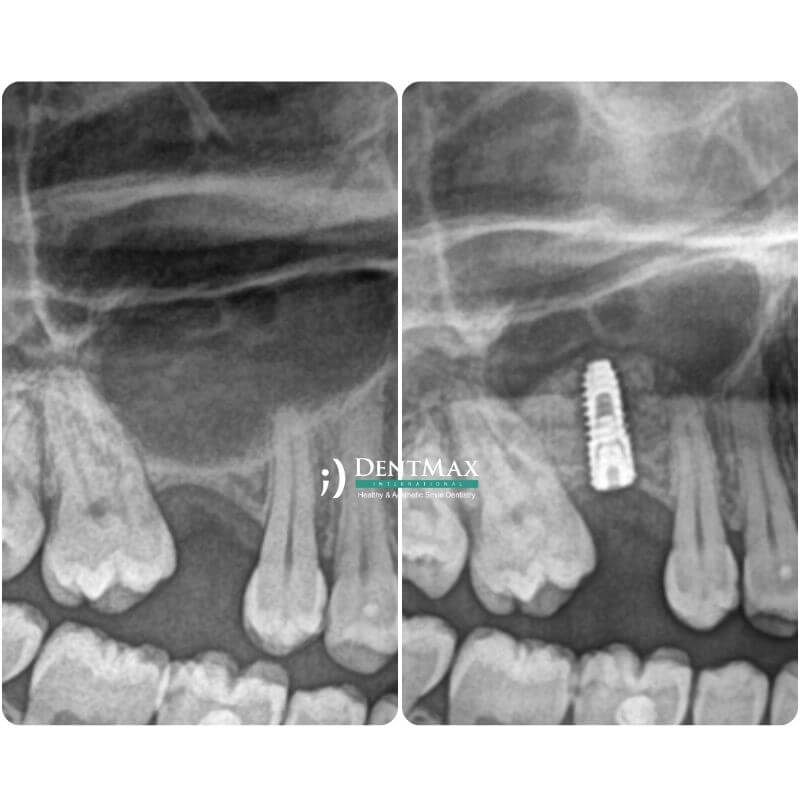

Костная пластика (Костная пудра)